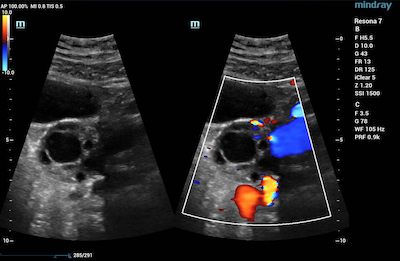

- Reproductive System – CDI is advantageous in evaluating uterine abnormalities, assessing the ovaries and testes for the absence of blood flow in instances of torsion, and even penile Doppler for various male reproductive conditions.

Color Doppler Imaging of Ovarian Perfusion